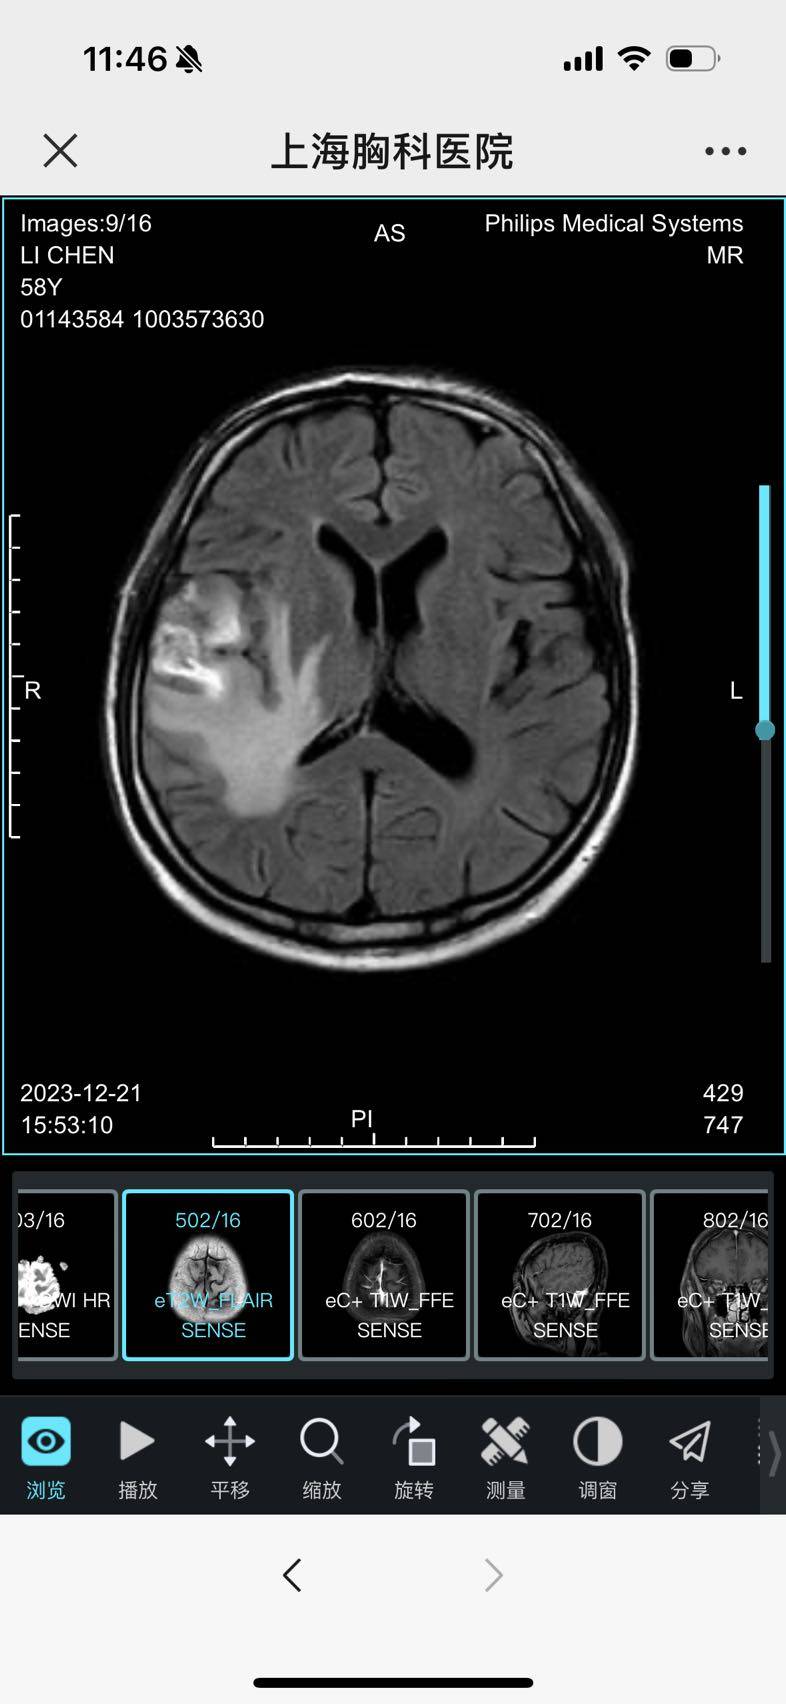

四次化疗结果出来了,喜忧参半。肺部控制住了,维持稳定。

头部肿瘤又长大了一些,速度还是比较快的。虽大部份坏死,边缘还是有活性造成水肿,可能也会放大了肿瘤的大小吧。体感还不错,还能正常的工作、运动,旅游!

接下来,一边消水肿,试一个月伏美替尼双倍的效果,看看能不能控制一下头部肿瘤。马上就要迎来新的一年了,愿所有的晦气和2013年离我们远去,让我们张开双臂拥抱好运和2014年吧!